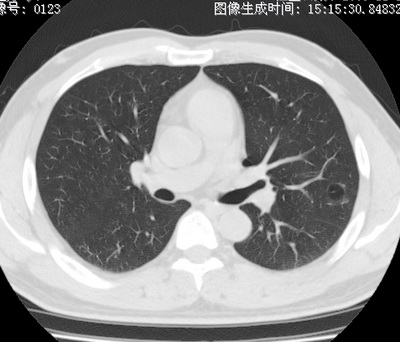

以下是引用zhao_bin2008在2010-1-4 20:15:00的发言:[br]先天性肺囊肿或小的肺隔离症?

以下是引用卜一在2010-1-4 22:09:00的发言:[br]先天性肺囊肿或小的肺隔离症?支持!

以下是引用zsl6918在2010-1-5 5:23:00的发言:[br]良性改变!肺囊肿,先天性支气管闭锁,血管畸形等均有可能。

以下是引用影像之路在2010-1-6 11:10:00的发言:[br]腺癌,最终的病检有些出乎意料之外,术前同志们大多考虑为肺囊肿或小的肺隔离征 [br]回过头来看 小结节呈分叶状,其内侧有一条较粗的静脉供血或许能成为支持诊断腺癌的理由